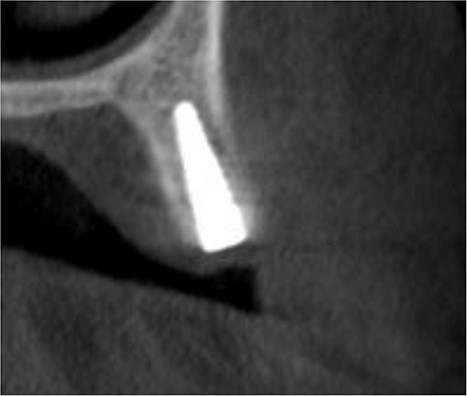

A 35-year-old female patient presented to the Oral and Maxillofacial Surgery department at university hospital with chief complaints, desire to replace the right upper canine with dental implant. Patient was recommended an Orthopantomography (OPG) and cone beam computed tomography (CBCT) for planning the implantation. OPG showed an appropriate mesiodistal distance for dental implant placement. A CBCT scan showed insufficient alveolar ridge width for dental implant placement. The average width of the alveolar ridge before the surgery was 4.56 mm. The treatment plan was made by placing a 3.5 mm diameter dental implant in conjunction with a guided bone regeneration procedure using a prefabricated L-shaped titanium mesh.

Under local anesthesia with 4% articaine solution, a full-thickness flap was raised to expose the alveolar ridge. The initial point was marked with a point drill. The implant site was first prepared with a 2.2 mm pilot drill, and then with a 3.3 mm drill. After preparing the implant bed, we noticed the disappearance of the coronal and middle third of the buccal wall, exactly as planned. A submerged implant system (INNO submerged implant; Cowellmedi Inc, South Korea) was inserted according to the manufacturer’s instructions (Fig. 1). The insertion torque value was 33 N.cm. several perforations were prepared at the buccal side of the recipient bone bed using a small round bur for better blood supply. An allogeneic bone graft material (Cortical Cancellous powder; TRCIR Co, Iran) was used to reconstruct the buccal plate. A prefabricated L-shaped titanium mesh has been adapted to fit the shape of the alveolar ridge to be reconstructed, and it was fixed to the implant with a cover screw (Fig. 2). The flap was mobilized to permit a tension-free primary closure, was closed with 4–0 silk sutures. Sutures removal was done after 1 week. The surgical sites were left to heal for 6 months.

Inserting a dental implant of 3.5 mm diameter and 10 mm length into its prepared bed. The implant was completely surrounded by bone in its apical third only.

The implant was exposed 6 months postoperatively and the healing caps were placed. CBCT scans were taken to assess gained bone width (Fig. 3). The mean alveolar ridge width before surgery was 4.56 mm. After 6 months, the mean alveolar ridge width was 7.23 mm.

A CBCT scan 6 months after surgery showed formation of new bone buccally, and the entire dental implant being surrounded by bone.